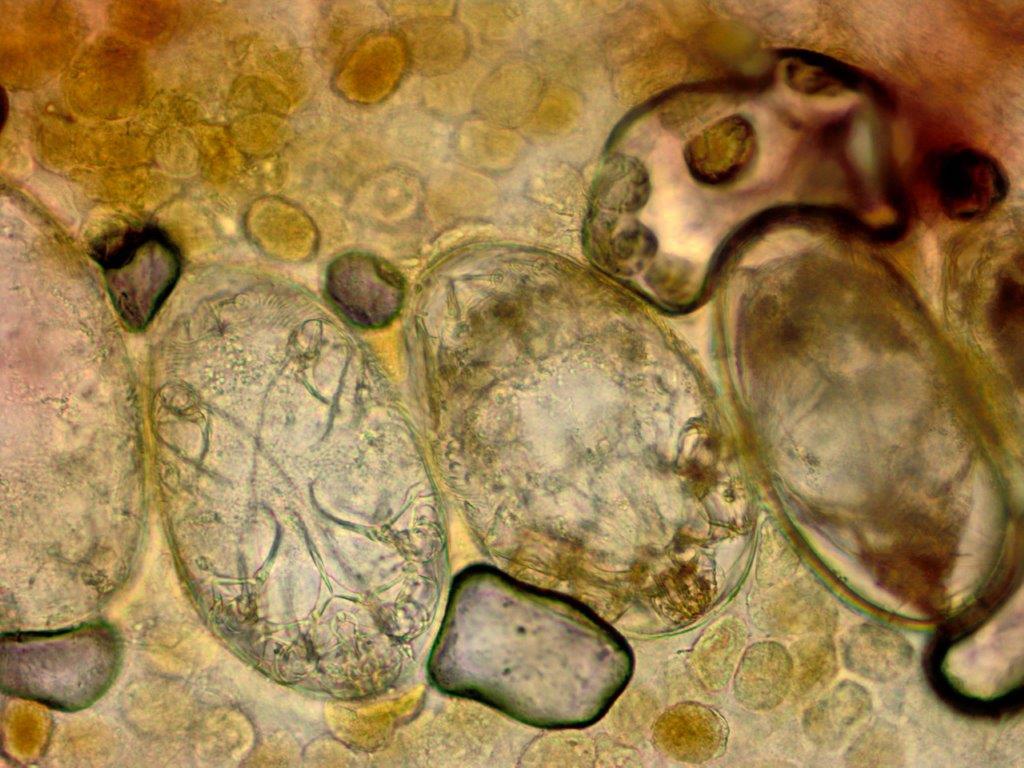

De huidschilfers zitten vol mijten en jongere mijtenstadia. Het volstaat om wat schilfers af te schrapen van een hyperkeratotisch schilferend gebied en daar een KOH-preparaat van te maken, daar moeten dan tientallen mijten en eieren in te zien zijn om de diagnose scabies crustosa te mogen stellen. Deze schilfers zijn zeer besmettelijk. Door het krabben kunnen de met schurftmijt beladen huidschilfers door de kamer dwarrelen en anderen besmetten (verzorgers, medepatiënten, bezoekers, huishoudelijk personeel). Als een patiënt met scabies Norvegica in een instelling verblijft is dat een risico voor het personeel en gelden strengere isolatiemaatregelen. Iedereen die in de kamer geweest is moet preventief worden behandeld met éénmalig ivermectine. Zie ook de richtlijn van het RIVM voor de aanpak van een uitbraak van scabies. In instellingen indien mogelijk de patiënt om de week verplaatsen naar een schone kamer en de oude kamer 1 week niet betreden.

Scabies mijten in het KOH preparaat

Mijten bij scabies crustosa Mijten bij scabies crustosa